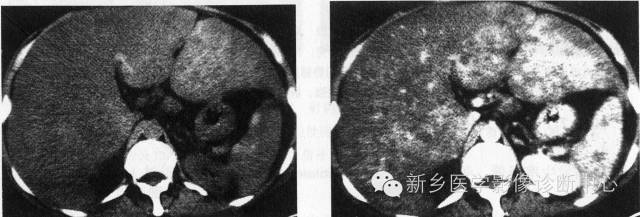

12、肝硬化再生结节

平扫多表现为高密度,增强扫描不同程度强化,延时扫描呈等密度。

小结节的RN 在螺旋CT 的平扫及动态增强扫描中常不能发现, 因为肝实质的密度都较均匀。少数大结节的RN 在增强扫描中可见, 表现为平衡期呈略低密度, 而更少数的较大的RN 在增强扫描的三期中均呈略低密度, 类似于少血供的HCC。

肝硬化结节的病理:肝细胞大量坏死,肝细胞肥大再生而形成肝硬化结节,同时伴有肝内广泛纤维化致肝小叶结构紊乱,从而导致肝脏收缩、体积缩小及肝脏表面高低不平。纤维化,结节再生,变性坏死和脂肪变性等病理改变致肝脏密度的高低不均。病理上分为3型,直径大于3cm的为大结节型,最大可达12cm,直径位于1~3cm为小结节型,二者混存为混合型;有研究表明,肝硬化再生结节以门脉供血为主,缺乏动脉供血。

肝硬化再生结节平扫一般为等密度或高密度;注射造影剂后动脉期强化不明显,在门脉期及延迟期肝硬化再生结节与肝实质密度趋向一致,这是诊断肝硬化结节的主要征象;肝硬化结节是发生在肝硬化基础上的良性增生结节,肝硬化,脾大,腹水,脾、门静脉迂曲也是诊断肝硬化再生结节的一个征象。肝脏的密度由平扫时的不均匀变为增强后的均匀,这都是诊断肝硬化结节的重要征象。

需与肝癌鉴别,肝癌平扫绝大多数呈低密度,少数呈等密度或高密度,肝癌瘤灶内的密度更低区有其多数性,多形性及多层面显示的特征;肿瘤边缘的“晕圈征”和CT平扫边缘不清而常规增强后缘变清楚且肿瘤随之变小及周围的“卫星”结节直径3~5cm时,其动脉期强化一般是不均匀的,极少数是均匀的;增强过程癌结节造影剂的充盈呈“快进快出”的表现。值得注意的是肝癌与肝硬化结节共存时,容易漏诊。